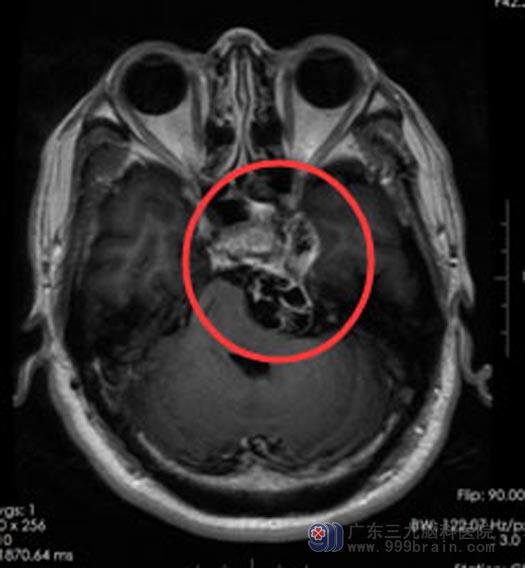

一个月前,症状变得越来越重,不但发作频繁还出现了头晕。后来,听朋友介绍,赵先生来到了广东三九脑科医院综合神经外科。MR结果示:左侧鞍旁至左侧桥小脑角区囊实性占位性病变,考虑三叉神经鞘瘤。

三叉神经起源于脑干,跨越多个颅底孔道,分布范围深在,周围毗邻脑干、海绵窦、颈内动脉及多条颅神经。体积较大的三叉神经鞘瘤,手术很具有挑战性。

在充分的术前准备后,由鲁明副院长为赵先生实施“左侧跨中后颅窝三叉神经鞘瘤切除术”。术中见肿瘤有完整的包膜,丰富的血运,和三叉神经粘连,显微镜下充分保护血管与神经,完整切除了肿瘤。